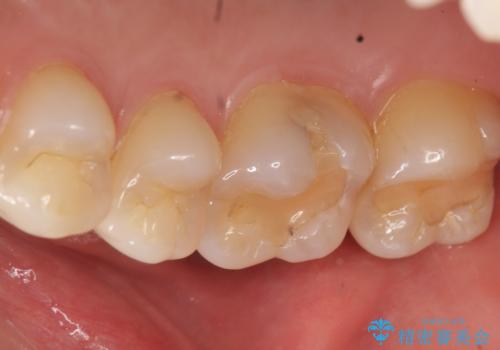

- 奥歯にフロスを通すとにおいがすることを気にされ、来院された患者様です。

精査したところ、奥歯に充填された保険内のコンポジットレジンの適合が悪いことにより、汚れがたまりやすい状態でした。

不適合なレジンを除去し、セラミックインレーによる治療を行いました。(右上76左上67右下7の計5本)